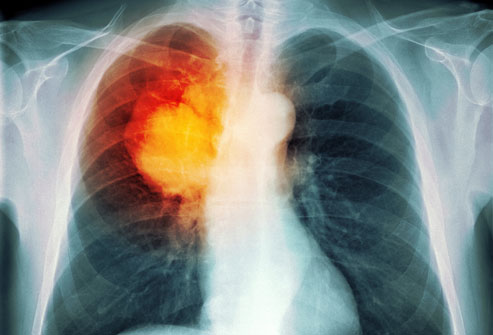

폐암의 진단은 주로 의사가 환자의 증상, 진료 이력, 가족 질환 여부, 기침 상태, 체중 변화, 기침에서 나오는 가래의 색깔 등을 질문하고, 폐 X선 촬영, 생리학적 검사, 폐기능 검사, 조영술 등을 통해 진단합니다.